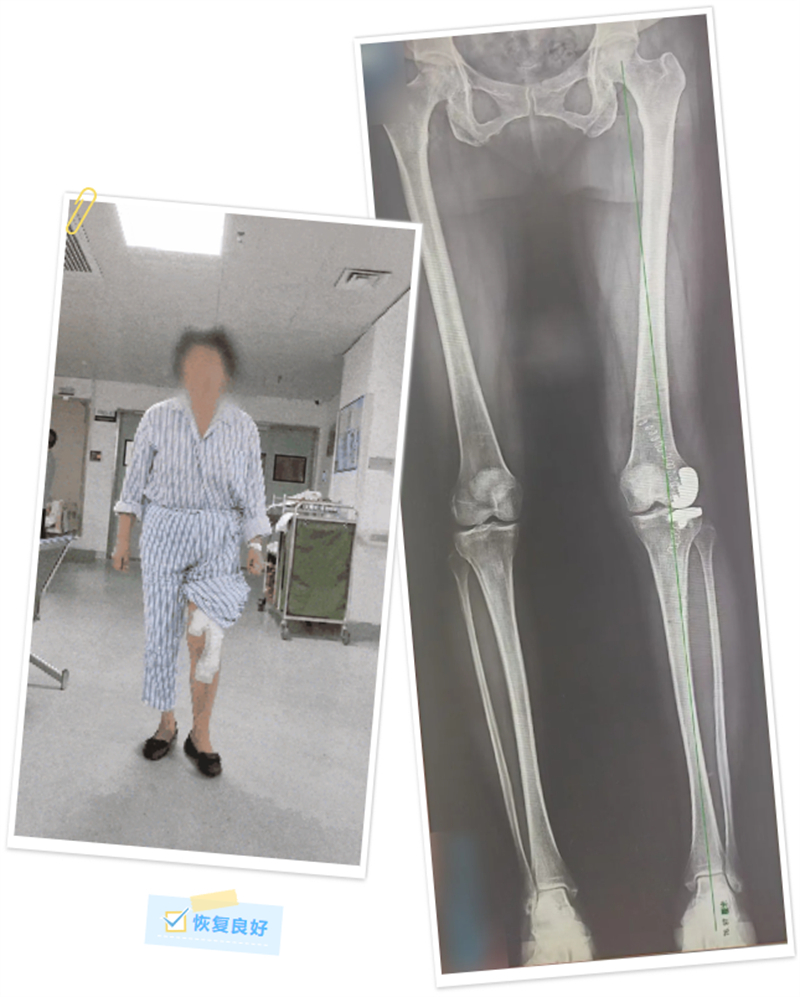

術(shù)前,手術(shù)團(tuán)隊(duì)將患者的下肢CT數(shù)據(jù)錄入機(jī)器人系統(tǒng)后,運(yùn)用計(jì)算機(jī)對(duì)假體的位置及型號(hào)參數(shù)進(jìn)行了詳細(xì)的規(guī)劃和模擬,術(shù)中再次對(duì)患者的下肢力線及軟組織張力進(jìn)行了實(shí)時(shí)校對(duì)和調(diào)整。在機(jī)械臂連接的專(zhuān)用工具輔助下,最終成功將假體植入,并獲得了較好的軟組織張力平衡和活動(dòng)度,同時(shí)糾正了患者的下肢力線。

術(shù)后,覃女士恢復(fù)良好,還送來(lái)了寫(xiě)著“醫(yī)術(shù)精湛、醫(yī)德高尚”的錦旗表示感謝。